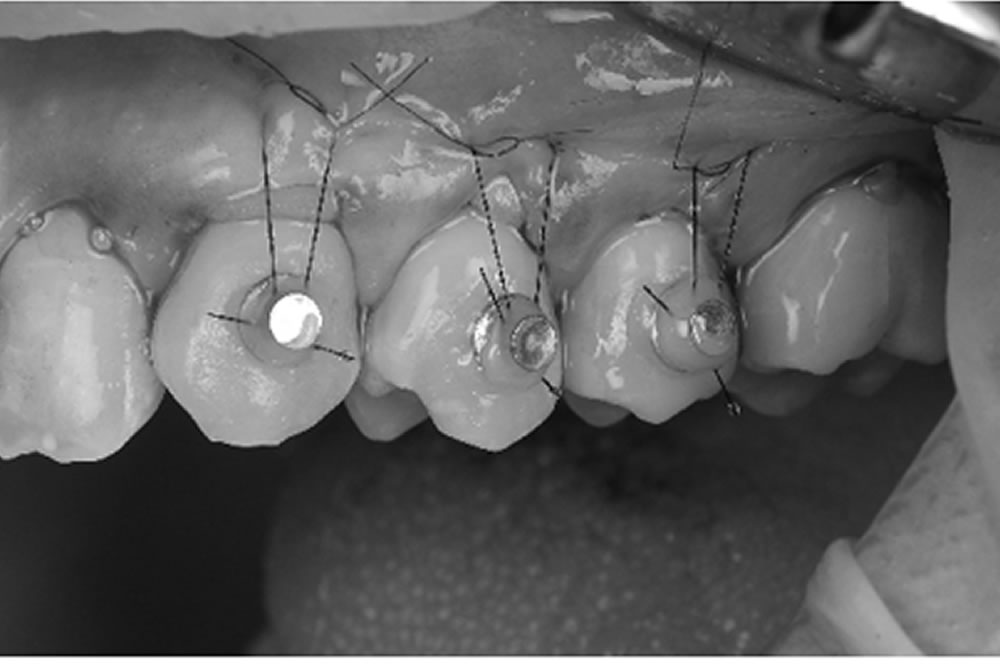

しかし、近年ではマイクロスコープと小型の清掃器具を併用することにより、歯ぐきを切ったり、痛みを伴ったりすることなく、歯周ポケットの奥深くに付着した歯石の確認、除去が可能となりました。患者さまの負担を抑えながら、より効率よく歯周病の改善が期待できます。

当院で実施した重度歯周病治療【MINST】の症例

初診時(上写真)、右下6番目の歯は今にも抜け落ちそうな状態でしたが、重度歯周病治療【MINST】によって、症状を改善し、術後1年後(下写真)には歯周組織もしっかりと再生しました。

マイクロスコープで歯周ポケット5mm以上の歯石を除去している動画

この動画は実際にBiVi歯科・矯正歯科にて、歯周ポケット5mm以上の歯石を除去している様子です。肉眼、もしくは数倍の拡大鏡ではとてもではありませんが、見えません。一般歯科では歯周外科か抜歯のどちらかを宣告されるケースと思いますが、こちらの患者さまは歯周病が改善し、抜歯や外科処置は一切行わずに済みました。